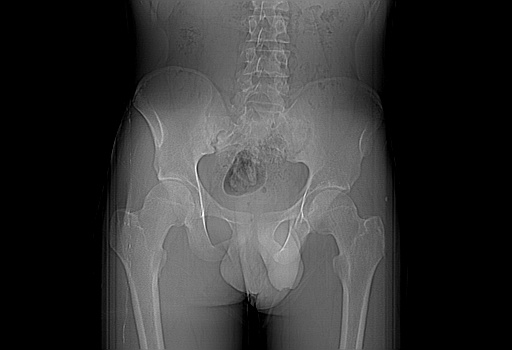

患者男性,18岁 腰腿痛1年  骶髂关节改变本人考虑强直性脊柱炎。

两侧骶髂关节骨质破坏,关节面毛糙,符合强直性脊柱炎骶髂关节改变。

两侧骶髂关节骨质破坏,关节面呈锯齿样改变关节间隙变窄,考虑强真性脊柱炎

双侧骶髂关节关节间隙变窄,边缘毛糙,关节面硬化,可见囊变!符合强直变现!

两侧骶髂关节骨质破坏以髂骨为主,间隙变窄,强直性脊柱炎